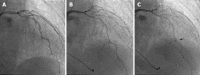

Coronary spasm is caused by a transient coronary narrowing due to the constriction of epicardial coronary artery, which leads to myocardial ischemia. More than 50 years have passed since the first recognition of coronary spasm, and many findings on coronary spasm have been reported. Coronary spasm has been considered as having pivotal roles in the cause of not only rest angina but also exertional angina, acute coronary syndrome, and heart failure. In addition, several new findings of the mechanism of coronary spasm have emerged recently. The diagnosis based mainly on coronary angiography and spasm provocation test and the mainstream treatment with a focus on a calcium-channel blocker have been established. At a glance, coronary spasm or vasospastic angina (VSA) has become a common disease. On the contrary, there are several uncertain or unsolved problems regarding coronary spasm, including the presence of medically refractory coronary spasm (intractable VSA), or an appropriate use of implantable cardioverter defibrillator in patients with cardiac arrest who have been confirmed as having coronary spasm. This editorial focused on coronary spasm, including recent topics and unsolved problems.